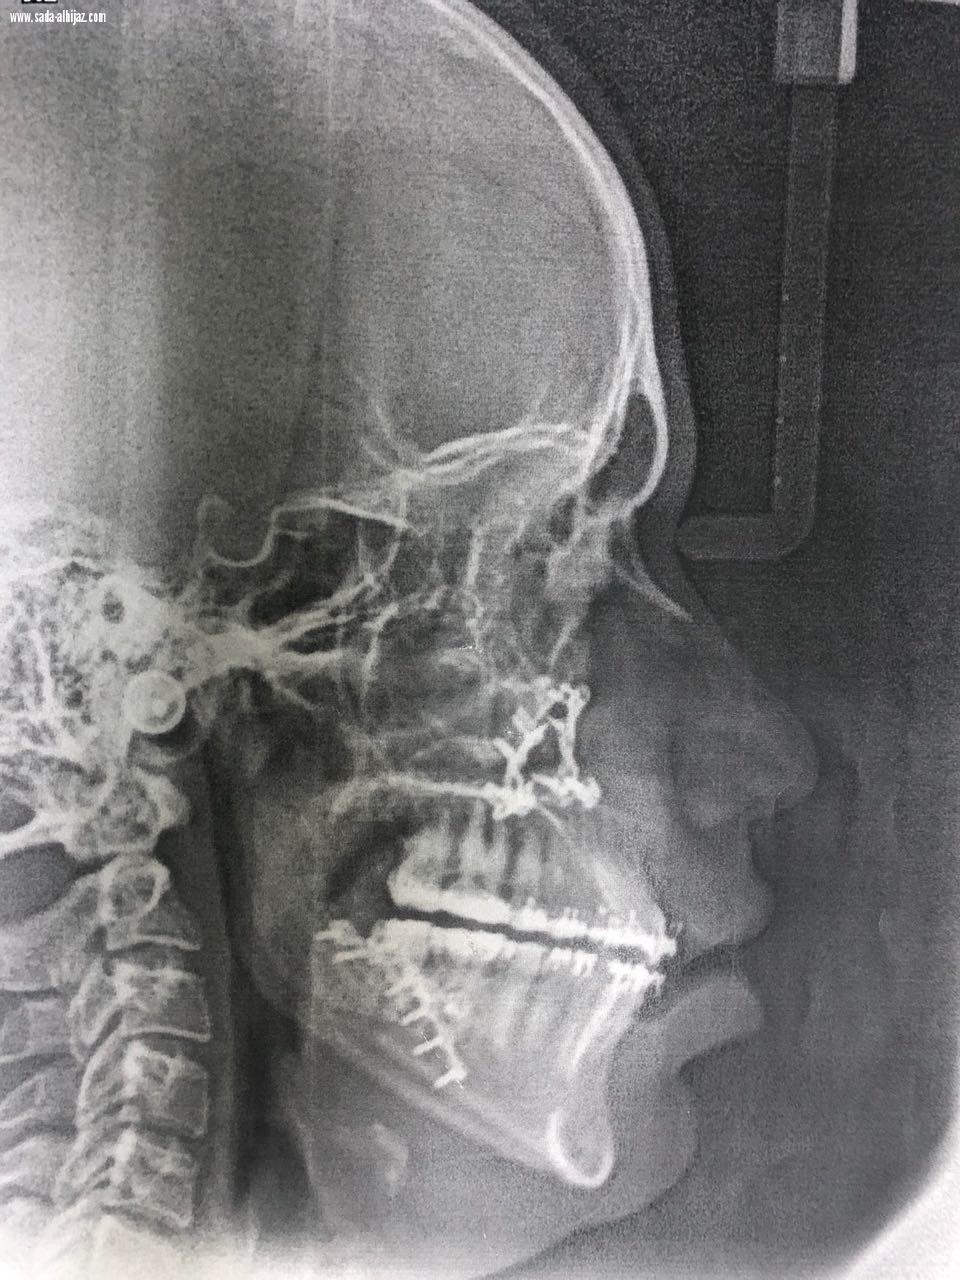

وبين الدكتور سعيد البلوي إستشاري جراحة الوجة والفكين ورئيس القسم بالمستشفى أن المريض حضر الى القسم محولاً من أحد المستشفيات وهو يعاني من تقدم حاد بالفك السفلي مما سبب له تشوه بمظهر الوجه وهو ما انعكس سلباً على حالته النفسيه، وبعد التنسيق مع مستشفى أحد تم عمل الأشعة والفحوصات اللازمة كإجراء أولي.

وأضاف د. البلوي بعد ذلك تم عمل إجراء جراحي على نموذج تم عمله في معمل طب وجراحة الأسنان بالمستشفى قبل البدء بالعمليه فعلياً وبعد الإنتهاء من كافة الفحوصات اللازمة تم إجراء العملية للمريض وهي عبارة عن تقديم الفك العلوي بمقدار 2 ملم، وارجاع الفك السفلي بمقدار 4 ملم مع التدوير إلى جهة اليسار لإصلاح خط المنتصف تكللت بالنجاح ولله الحمد.